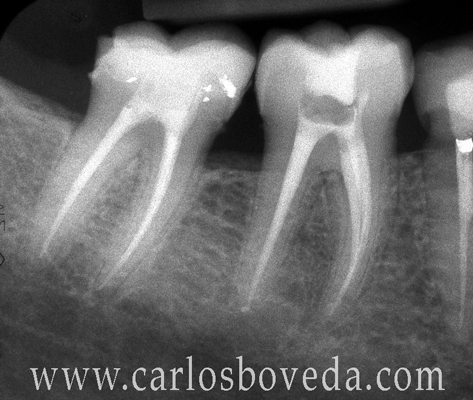

1. 10